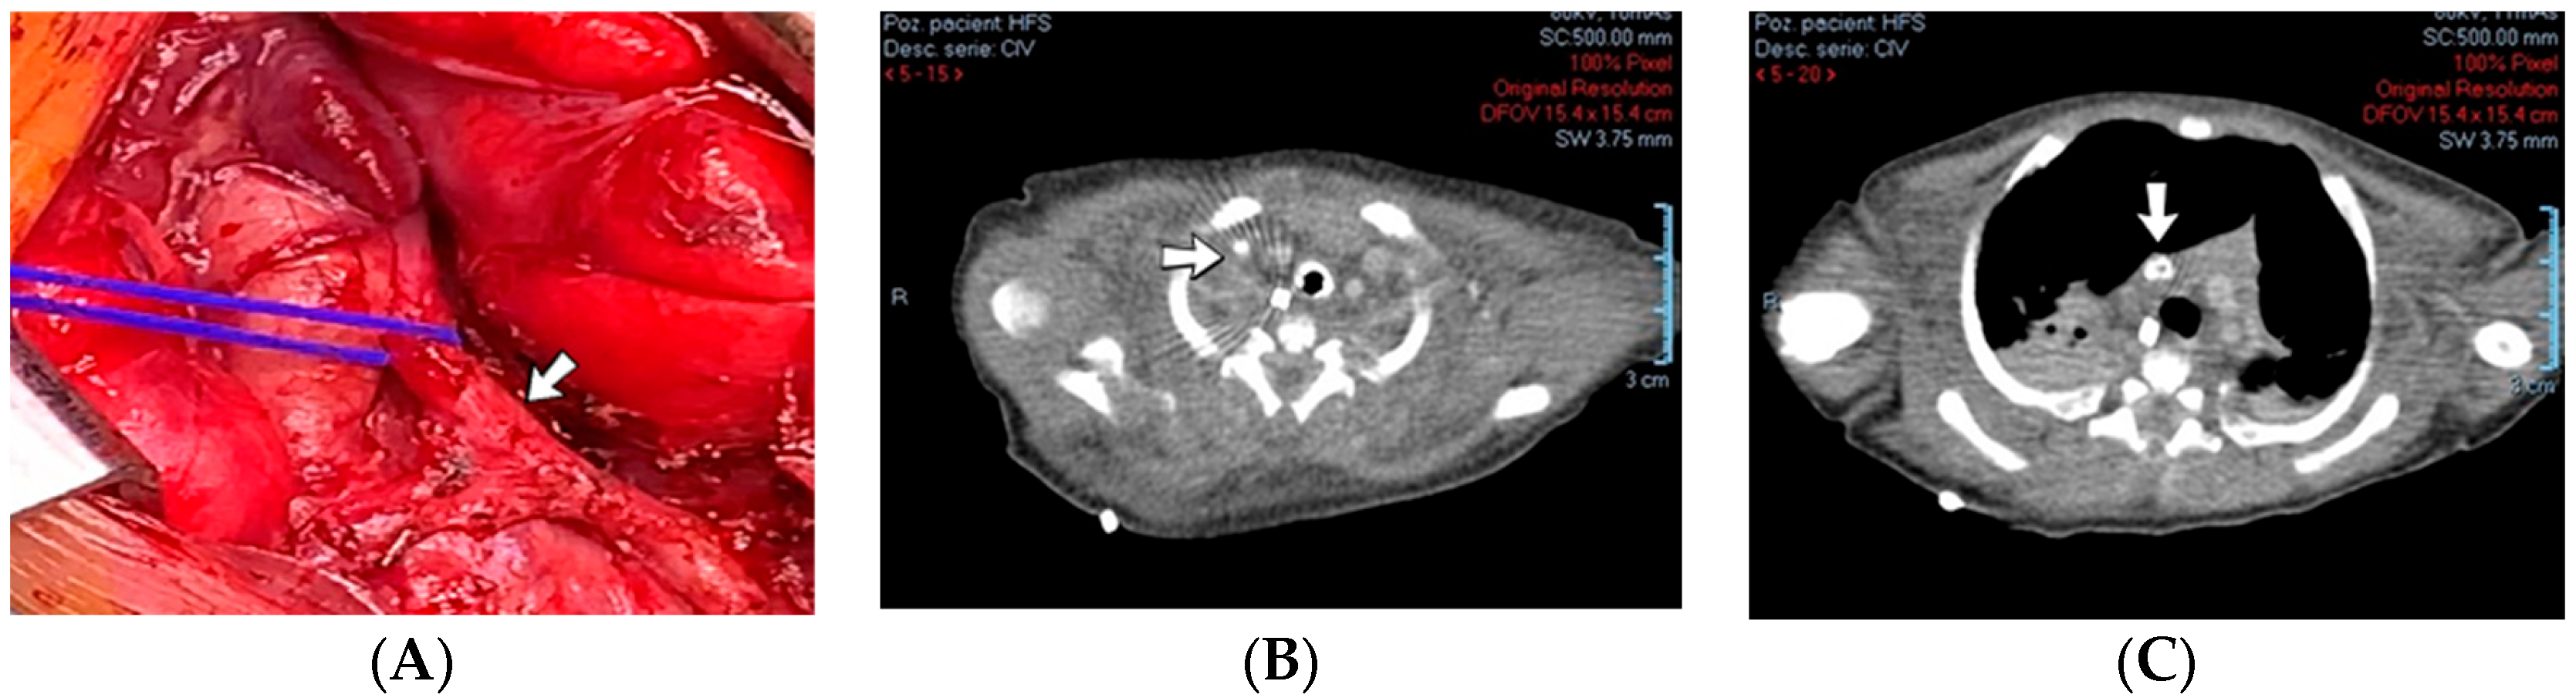

4.35. Case No. 35—Home Onset—Thrombosis of the Right Pulmonary Artery and Intracardiac Thrombosis

A 19-day-old male neonate (35–36 weeks, 2.20 kg) presented with thrombosis of the right pulmonary artery diagnosed on the same day at another pediatric emergency department, where treatment with continuous heparin infusion was initiated. The admission laboratory findings showed elevated c-reactive protein, modified coagulation tests (ongoing anticoagulation treatment), and elevated D-dimer tests. The cardiac ultrasound identified thrombi in the right atrium and ventricle (Figure 15). Therapy with heparin was continued, to which alteplase was added. After four days of anticoagulation and fibrinolytic therapy, the thrombi could no longer be noticed on ultrasound or CT scan.

Figure 15.

Intracardiac thrombosis was identified on cardiac ultrasound: in the right pulmonary artery (A), the right atrium (B), and the right ventricle (C).

Genetic testing confirmed inherited thrombophilia, with a positive MTHFR C677T homozygous gene mutation and Antithrombin, Protein S, and Protein C deficiencies. A mild elevation of PAI-1 levels was detected. There was limited information about the family history.